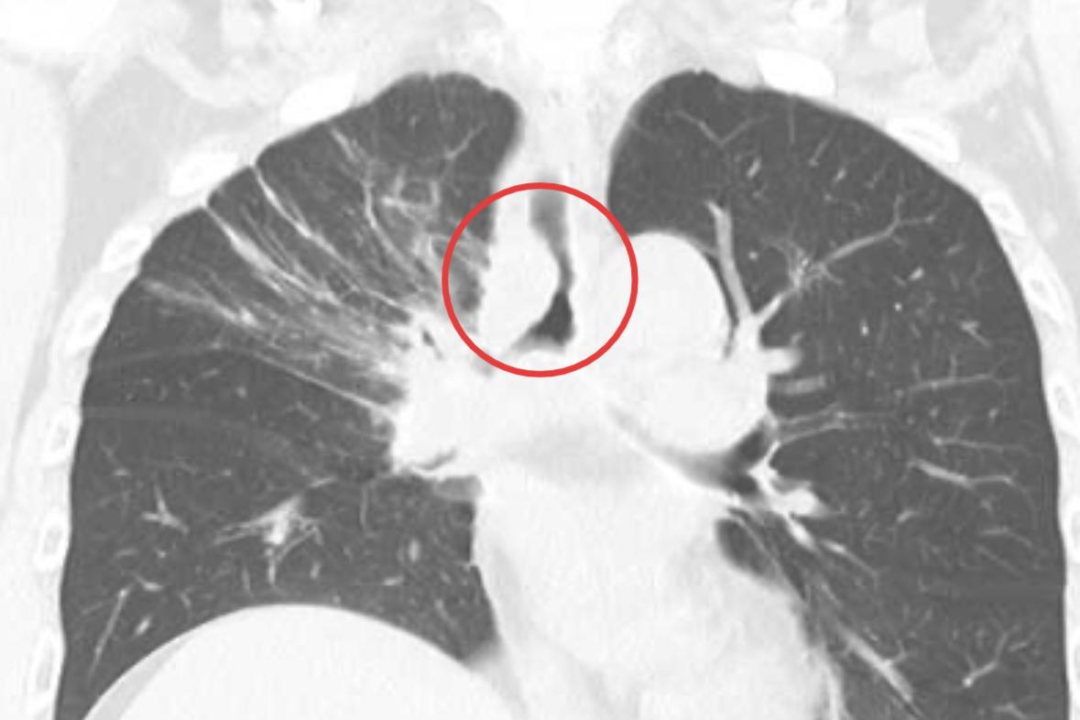

近日,贵州航天医院呼吸与危重症医学科紧急为一名主气道被肿瘤严重堵塞的肺癌患者成功实施了全麻硬质支气管镜下气道内综合治疗术,生动诠释了医者对生命的敬畏,也体现了该团队以技术守护生命的深厚功底。 53岁的陈先生(化名)近半年来感觉气促逐渐加重。5个月前,他在外院确诊为右肺中央型鳞状细胞癌,使用了化疗及免疫治疗。最近半个月,喘息、呼吸困难进一步加剧,已连续多日因严重呼吸困难无法平卧,外院胸部CT显示:肿瘤已侵犯并导致主气道(隆突水平)重度狭窄甚至接近闭塞,存在急性窒息风险。鉴于气道梗阻进展迅速且已超出常规药物及支持治疗的缓解能力,外院评估暂不具备开展介入性气道开通的条件,病情危重,亟需紧急气道干预。 患者就诊于贵州航天医院时,已处于明显呼吸衰竭状态,血氧饱和度一度跌至79%(正常人一般在95%以上),生命垂危。 时间就是生命!经我院呼吸与危重症医学科呼吸介入团队紧急评估,该患者为高危中央型气道重度狭窄,病情危急,随时存在因气道完全阻塞导致急性呼吸衰竭甚至窒息的风险。当务之急是立即进行气管镜下精准评估,并根据狭窄位置、形态与程度,制定个体化介入治疗方案,以迅速解除气道梗阻,为后续综合治疗争取时间。 在与患者及家属沟通病情并征得同意后,呼吸介入团队立即在静脉舒适麻醉下行电子支气管镜检查,从镜下看到患者气管中下段被肿瘤组织阻塞,管腔狭窄高达80%,并且肿瘤呈浸润性生长侵犯至左、右两侧主支气管,于是团队当机立断,转为实施全麻硬质支气管镜下气道内综合治疗术。 医生将硬质支气管镜(一根中空的金属管道)经口置入患者主气道,在确保通气的同时,为后续操作建立了稳固的“工作通道”。手术中,首先在气管内严重狭窄处实施高频电刀切除部分肿瘤组织,然后再用高频电凝对基底部和易出血部位进行精准消融及止血,将堵塞“生命通道”的肿瘤逐步清理。 高频电刀切除 部分肿瘤组织 高频电凝 消融 由于肿瘤侵犯范围较大且生长快,单纯切除后气道壁仍有塌陷及再次阻塞的风险,为确保气道长期通畅,团队在气管狭窄最严重的部位,精准置入Y型镍钛合金覆膜气道支架。支架像一把撑开的“小伞”,瞬间将狭窄的气道撑开,恢复了气流的顺畅通过。 置入Y型镍钛合金覆膜气道支架 术后,陈先生转入病房进一步观察治疗,氧饱和度迅速回升至正常水平,呼吸困难随即缓解。这场成功的急救,不仅畅通患者的呼吸,也使其重获接受后续抗肿瘤治疗的机会。 贵州航天医院精品技术 硬质支气管镜介入治疗 硬质支气管镜介入治疗是处理复杂中央气道狭窄与阻塞的关键核心技术,本身是一个中空的金属管道,它在手术中扮演着多重关键角色: 可靠的通气保障:在全麻下,它本身可作为通气管道,维持患者在整个手术过程中的呼吸,为医生在气道内的复杂操作提供了充足的安全时间和稳定的操作平台。 稳固的操作通道:其宽阔的管腔允许多种治疗器械(如电刀、支架、冷冻探头等)同时或交替进入,便于进行高效、综合的介入治疗。 处理大出血能力强:对于富含血管的肿瘤,操作中一旦发生出血,硬镜能快速压迫止血或保证吸引效率,是处理高风险出血的重要安全保障。 贵州航天医院呼吸与危重症医学科是国家临床重点专科建设单位、贵州省医学重点学科、临床重点专科、贵州省基层医院介入培训基地,遵义市医学重点学科、临床重点专科,是贵州省内呼吸疾病诊疗规模最大、诊疗项目最全的呼吸疾病品牌科室。现开放床位350张,设有4个病区、RICU、呼吸介入诊疗中心、慢病康复治疗中心和呼吸疾病研究中心实验室,在肺癌与肺结节、慢性阻塞性肺疾病、肺炎、肺结核等呼吸系统疾病的诊疗方面形成了区域特色优势。 贵州航天医院 呼吸与危重症医学科专家简介 廖江荣 国务院政府特殊津贴专家 遵义市呼吸疾病临床医学中心 学科带头人 二级教授 硕士研究生导师 主任医师 学术任职: 亚洲冷冻治疗学会副主席 中国医药教育协会介入微创专业委员会呼吸分会副主任委员 中国防痨协会超声专业委员会副主任委员 中国抗癌协会肿瘤微创治疗专业委员会常务委员 中国防痨协会多学科诊疗专业委员会常务委员 中国医疗保健国际交流促进会结核病学分会常务委员 第一届中国人体健康科技促进会呼吸介入专业委员会常务委员 中国抗癌协会第一届肿瘤组织间植入治疗专业委员会常务委员 西部呼吸介入联盟副理事长 贵州省医学会呼吸病学分会第六届委员会副主任委员 贵州省中西医结合呼吸专业委员会副主任委员 贵州省医学会结核病分会常务委员 遵义市呼吸内科专业医疗质控中心主任委员 遵义市中西医结合学会理事长 专业擅长: 呼吸系统(肺)疑难病的诊断及危重病的抢救,呼吸系统(肺)感染性、疑难性疾病介入快速诊断(ROSE),尤其在肺癌、肺小结节早期诊断,肺癌微创综合靶向治疗,难治性、复治性、重症肺结核诊疗,硬质支气管下复杂性气道狭窄诊治,纤支镜介入治疗气道肿瘤、结核、气道狭窄(球囊扩张、支架植入、高频电刀、氩气刀、冷冻、灌洗、注药、微波消融),间质性肺疾病的诊疗上具有极高水平;带领团队勇于创新,在贵州省率先开展多项新技术、新疗法,如CT引导下及纤支镜下I125粒子植入及CT引导下微波、冷冻消融介入治疗肺癌等多项新技术,带动了贵州省肺部疾病的介入治疗水平提高。 蒋 婷 贵州航天医院党委委员、副院长,副主任医师 专业擅长:从医20余年,在呼吸系统疾病、介入呼吸病学、肺部结核、肺部肿瘤等方面具有丰富的临床经验和专业技能,尤其是慢性阻塞性肺疾病、支气管扩张、肺结核、耐药肺结核、肺癌、胸腔积液等肺部疾病的诊治、微创介入、危重病患者抢救。 现任中国防痨协会结核病与糖尿病专业分会副主任委员,中国女医师协会第一届介入专业委员会委员,贵州省基层呼吸疾病防治联盟-间质性肺疾病联盟委员,贵州省防痨协会第七届理事会理事,贵州省中西医结合学会呼吸专业委员介入呼吸病学组委员,贵州省遵义市中医药学会中西医结合肺病(呼吸)分会副主任委员,贵州省遵义市中医药学会中医肿瘤专业委员会常委;发表论文数篇,参与并主持多项科研项目。 唐永江 四川大学华西医院 呼吸与危重症医学科 副主任医师 呼吸危重症医疗组长 香港中文大学博士 美国康奈尔大学访问学者 贵州航天医院 呼吸与危重症医学科 学科带头人 主要从事呼吸危重症(特别是呼吸重症感染)的临床及科研工作。 PCCM专培结业医师 中华医学会呼吸病学分会呼吸危重症学组秘书 中华医学会呼吸病学分会ECMO工作组成员 四川省医学会呼吸病学专委会介入学组委员兼秘书 发表文章20余篇,主持及参与多项国家自然科学基金及省卫健委基金。 周裕祥 呼吸、感染党支部书记,呼吸与危重症医学科总负责人,副主任医师 专业擅长:对经皮穿刺肺活检、肺结节、肺癌的微创介入诊疗具有丰富的临床经验。 贵州省中西医结合学会呼吸专业委员会介入呼吸病学组常务委员,中国医师协会呼吸医师分会介入呼吸病学工作委员会呼吸病血管介入学组委员,贵州省中西医结合学会呼吸学分会委员,遵义市医学会放射肿瘤治疗学分会委员,中国医药教育协会介入微创呼吸分会委员,北京健康促进会中青年专家委员会胸部疾病精准活检分委会委员;曾赴重庆医科大学RICU、珠海市人民医院介入科进修学习。 王 云 中共党员,呼吸与危重症医学科一病区主任,副主任医师 专业擅长:擅长呼吸系统常见病及疑难危重症、介入呼吸病学、肺部肿瘤疾病的诊治,尤其擅长快速现场评价(ROSE)技术。 贵州省中西医结合学会呼吸专业委员会介入呼吸病学组委员,遵义市中医药学会中西医结合肺病(呼吸)分会委员,贵州省中西医结合学会第六届呼吸专业委员会委员。 杨 芳 中共党员,呼吸与危重症医学科二病区、内镜中心主任,副主任医师 专业擅长:从事临床工作约20年,对呼吸危重病的救治有独到的见解,尤其擅长呼吸系统疾病的介入诊疗,对呼吸内镜下的诊治及经皮肺穿刺诊疗技术具有丰富的临床经验。 亚洲冷冻治疗学会委员,中国医药教育协会介入微创呼吸分会委员,西南结核病医院联盟第二届委员会秘书/委员,贵州省中西医结合学会第六届呼吸科专业委员会委员,贵州省中西医结合学会呼吸专业委员会介入呼吸病学组秘书,贵州省中西医结合学会呼吸专业委员会基层康复学组副组长,贵州水利电力医学科学技术会高原医学分会委员,遵义市中医院学会中西医结合肺病(呼吸)分会秘书/常务委员,遵义市医学会肿瘤学分会(第二届)委员,遵义市医学会放射肿瘤治疗学分会第二届委员;主持及参与科研课题多项,参编著作《呼吸内镜操作技术规范》、《介入结核病学》,发表论文数篇。 李桂凤 中共党员,呼吸与危重症医学科三病区主任,副主任医师 专业擅长:从事呼吸系统疾病、结核病学、介入呼吸病学、肿瘤综合治疗、呼吸康复等临床工作20余年,擅长呼吸内科常见病、多发病及疑难重症危重病症的诊治,尤其对重症疑难结核及耐药结核病、介入治疗(肺)呼吸系统疾病、呼吸危重病抢救等方面具有较高诊疗水平。 中国防痨协会非结核病专业委员会委员,贵州省中西医结合学会第六届呼吸专业委员会委员,贵州省康复学会睡眠障碍康复专业委员会委员,遵义市呼吸内科医疗质量控制中心委员,遵义市落实民生实事结核病筛查阅片专家组成员;主持及参与实用新型专利3项。 贵州航天医院 呼吸与危重症医学科简介 贵州航天医院呼吸与危重症医学科是贵州省内呼吸疾病诊疗规模最大、项目最全的呼吸疾病品牌科室。现开放床位350张,设有4个病区、RICU、呼吸介入诊疗中心、慢病康复治疗中心和呼吸疾病研究中心实验室,分设感染性疾病、呼吸疑难危重症、肺癌/肺结节、呼吸系统慢性疾病、肺结核、间质性肺疾病、呼吸微创介入、肺血管疾病等8个亚专业。 权威平台,学科引领 作为国家临床重点专科建设单位、贵州省重点学科、重点专科建设单位,遵义市首批呼吸重点学科、重点专科,科室获批成立了遵义市呼吸疾病临床医学中心、遵义市呼吸内科医疗质量控制中心,先后成为国家卫健委能力建设和继续教育肿瘤(肺癌)微创介入建设中心、国家呼吸医疗质量控制与管理哨点医院、贵州省县级医院微创介入诊疗中心、四川大学华西医院-遵义市呼吸系统疾病临床诊疗中心及贵州省博士创新站。 是亚洲冷冻治疗学会副主席单位(呼吸内镜)、中国医药教育协会“介入微创呼吸分会呼吸介入技术”培训中心、中国人体健康科技促进会“呼吸介入技术”培训协作单位、国家卫健委海医会呼吸分会ROSE专委会“诊断性介入肺脏病学快速现场评价”培训协作单位、中国肺癌防治联盟“贵州航天医院肺结节诊治”分中心、呼吸康复规范化建设达标单位、世界内镜医师协会常务理事单位、中国介入医学产业技术创新联盟肿瘤热消融中心理事单位、西南综合介入专科联盟副理事长单位、西部呼吸介入联盟副理事长单位;贵州省中西医结合学会呼吸学分会呼吸介入专委会主委单位、遵义市中医药学会中西医结合肺病(呼吸)分会主委单位。 是北京中医药大学东直门医院肺病优势专科联盟副主委单位、国家呼吸病临床研究中心•中日医院呼吸专科医联体单位、国家中西医结合医学中心•中日友好医院中西医结合医联体单位、广州医科大学附属第一医院(国家呼吸医学中心)重症肺癌专病联盟成员单位。 创新驱动,技术突破 率先开展多项省内前沿技术,其中,CT引导下I125粒子植入术、射频、微波、冷冻消融术治疗肺部恶性肿瘤,硬质支气管镜、经气管镜介入技术治疗气道肿瘤、结核、气道狭窄(球囊扩张、支架植入、高频电刀、氩气刀、冷冻、光动力、激光等),AI机器人辅助经皮、经气管镜介入应用,肺部(呼吸)感染性、疑难性疾病现场快速评价(ROSE)等诊疗技术的开展,进一步推动了呼吸疾病介入诊疗技术在贵州省基层医疗机构的发展应用。 人才引擎,科研转化 柔性引进厦门医学院附属第二医院柯明耀教授、上海交通大学医学院附属仁济医院吴学玲教授、中山医科大学附属肿瘤医院张福君教授、上海市胸科医院孙加源教授、南方科技大学医院周红梅教授、天津医科大学总医院冯靖教授7名国内顶尖专家并建立工作站,依托“四川大学华西医院帮扶合作中心-遵义市呼吸系统疾病临床诊疗中心及贵州省博士创新站”引入华西医院唐永江博士担任学科带头人,借助珠遵协作平台成立珠海市人民医院专家团队外周血管介入工作站,锻造多元人才梯队,推动临床、科研能力双提升。 在高质量完成临床诊疗工作的同时,科室积极投身于呼吸介入诊疗领域的科研工作,近三年主持及参与国家级、省部级、市厅级科研项目30余项,“慢性阻塞性肺疾病患者规范化呼吸康复真实世界研究”课题获得国家卫生健康委医药卫生研究发展中心批复立项。在国家、省级刊物发表学术论文100余篇(其中SCI收录20余篇),参编国家级专家共识、专著11部,持续探索呼吸内镜技术的新应用、新方法,不断推动学科前沿发展,将科研成果转化应用于临床实践,促进诊疗水平进一步提升。 辐射基层,责任担当 同四川、云南、重庆等七十余家县(市)级基层医院建立了“贵州航天医院呼吸与呼吸危重症专科联盟”,充分发挥学科优势,提供优势技术支持,每年通过省级以上学术会议及培训班(主办或承办)、专家下沉指导帮扶、接收进修人员等方式,为基层培养了大批医疗骨干,有力推动了西南地区呼吸疾病诊疗水平的整体提升。 贵州航天医院呼吸与危重症医学科,以精湛技术、前沿科研与责任担当,守护每一次呼吸! END